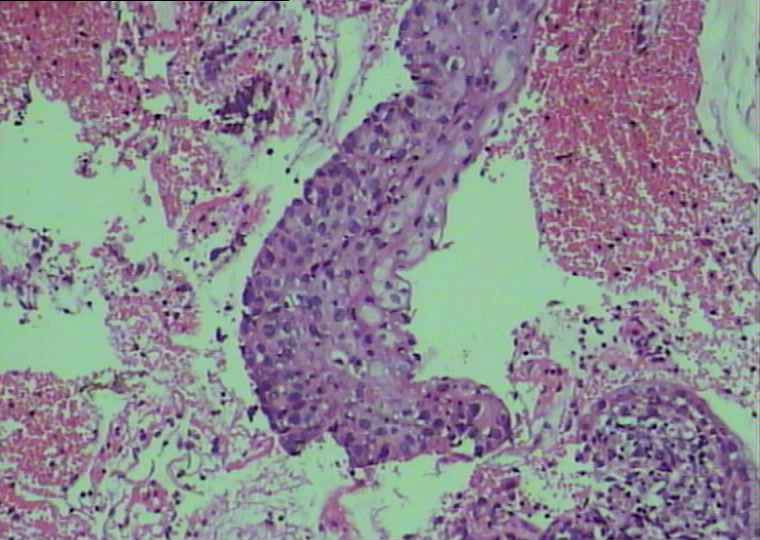

30岁宫颈活检

CIN2,累腺

宫颈高级别上皮内瘤变,累及腺体

CIN2-3累腺,锥切

CIN II-III,累及腺体

CIN-2,累腺。记杨斌老师说过,发现累腺,必是CIN-2以上病变。

高级别上皮内瘤变伴累腺

CIN2累及腺体

CIN2-3累腺

CIN3累腺

第一次发片子是CIN2级,第二次介于2-3之间。

年轻可以染染Ki67、P16、P53.确定一下级别。

因为咱们报2级只锥切就可以,3级要切子宫